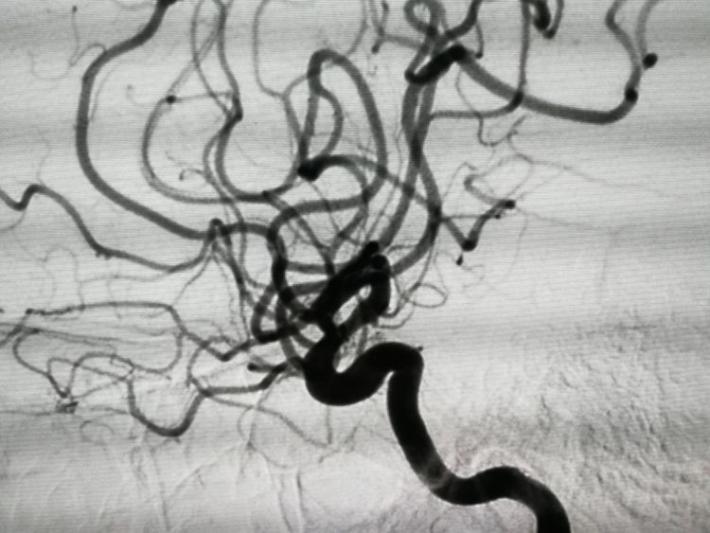

发病后6天(入院当天)DSA示:右侧前交通动脉瘤,右侧脉络膜前动脉瘤,仔细阅片,认为责任动脉瘤为前交通动脉瘤可能性大。原因如下:前交通动脉瘤约2x3mm大小,形状较狭长,瘤顶指向右侧前下方(也可解释蛛血部位)。而脉络膜前动脉瘤约1×1mm大小,形状较扁平,破裂可能性相对小些。

以原造影3D为依据,选择一角度再造影,见动脉瘤“若隐若现”,但路图上动脉瘤仍不显影,仔细观察血管,见同侧A1、回返动脉较前一日痉挛,分析系此因素加上动脉瘤小且窄颈的原因导致造影剂进入动脉瘤内太少,以致动脉瘤显影不良。考虑瘤体很小,路图上又不显示,盲目栓塞风险很大,决定终止手术,改行开颅夹闭。